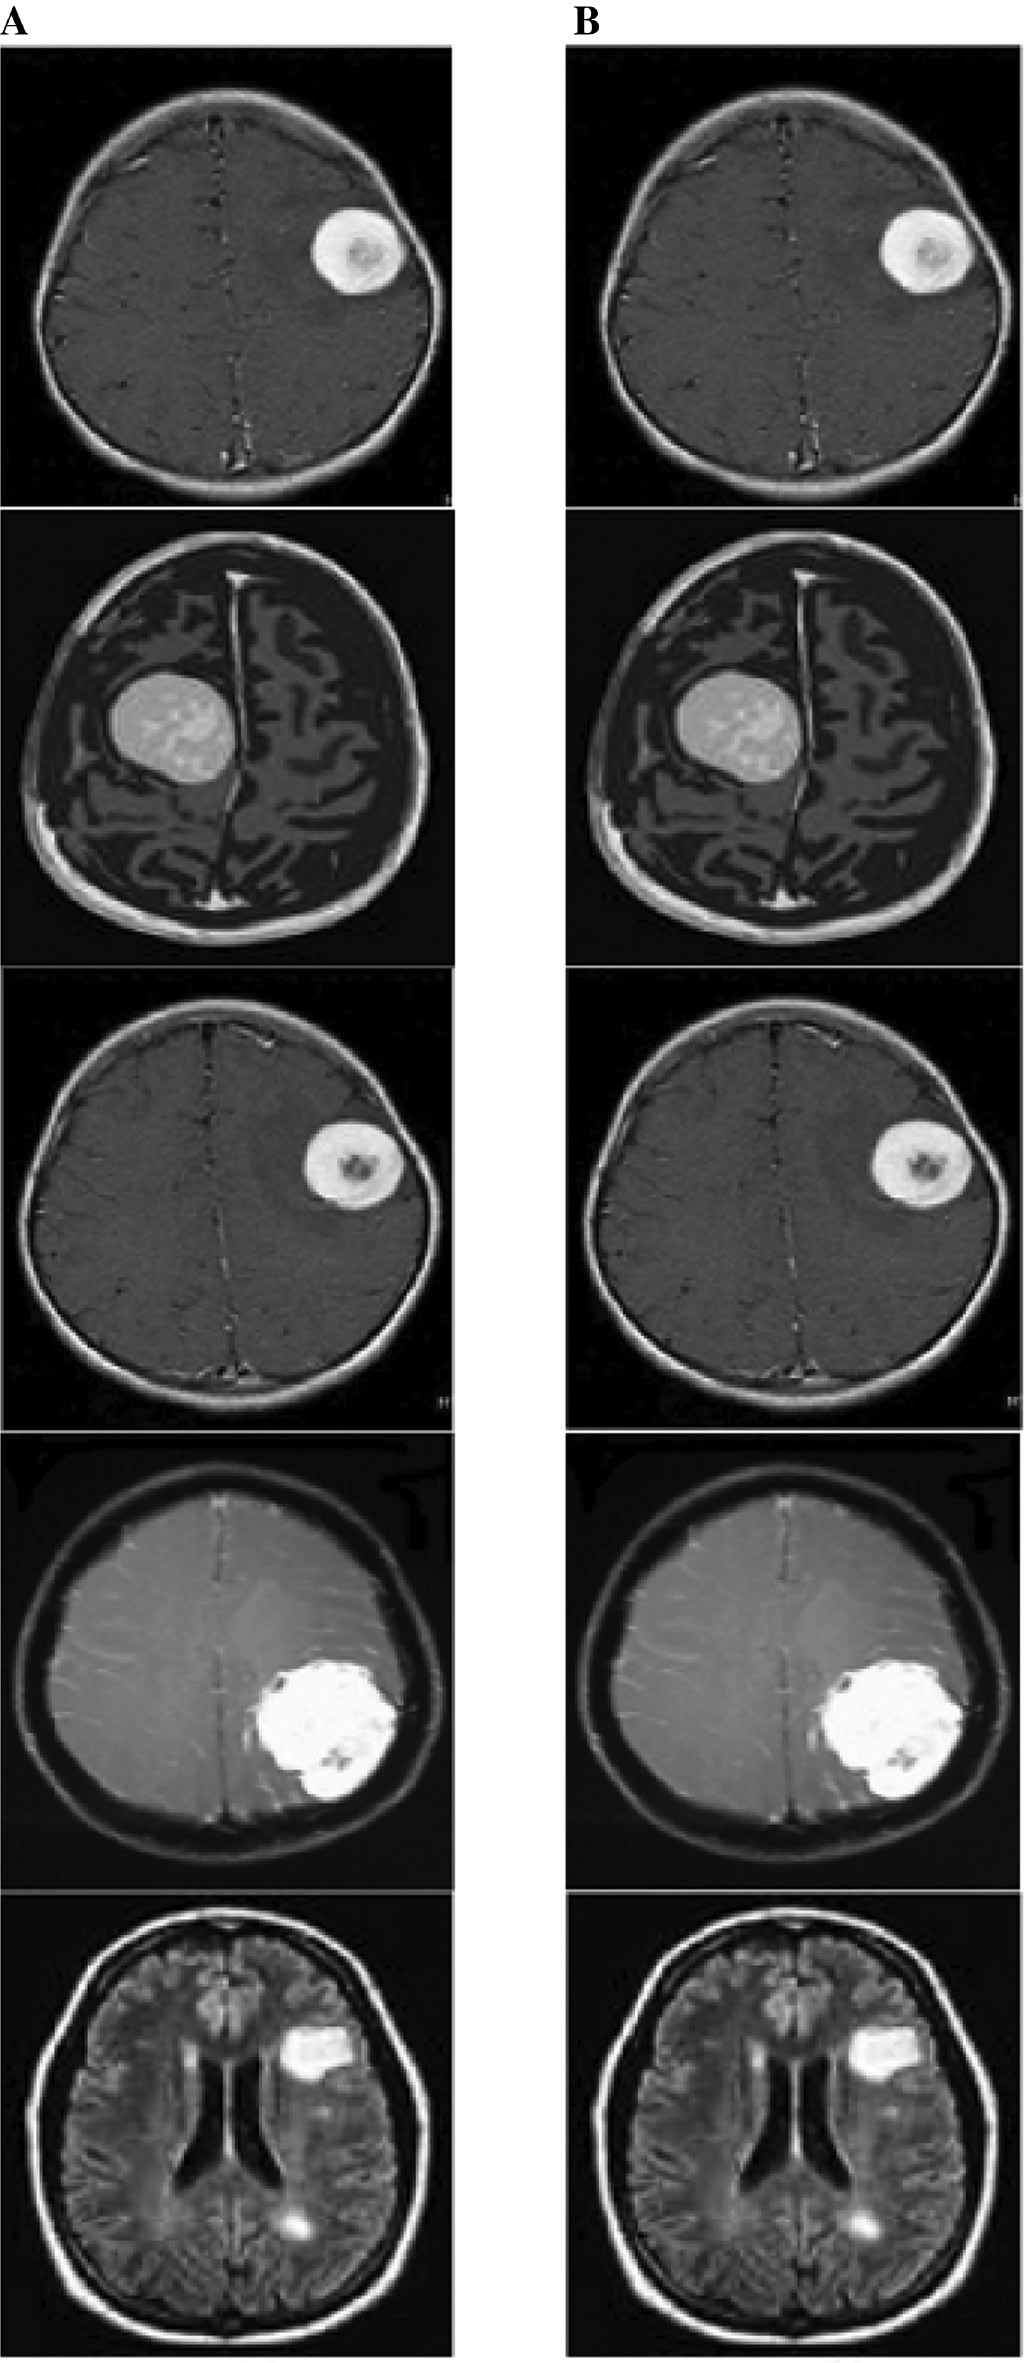

In this proposed watermarking, we hybridize lossless data compression and encryption techniques to embed EHR and image hash in medical images. The hybrid approach increases the security of the information (Table 3). Here, at first, we segment the ROI part from the image using the RG algorithm. Then, we encrypt the ROI part using SHA-256 and encrypt the EHR using the ECC algorithm. Thereafter, we concatenate the information and then compress it using the AC algorithm. The compressed bit stream is embedded into the medical image. Finally, we obtain the watermarked image. We used medical images of size 256×256. Figure 6 shows the original and watermarked images, and Figure 7 shows the experimental results of segmentation.

Figure 6: Experimental Output.(A) Input image. (B) Watermarked image.

(A) Input image. (B) Watermarked image.

Figure 7: Segmentation Output.(A) Input image. (B) Segmented ROI region.

(A) Input image. (B) Segmented ROI region.